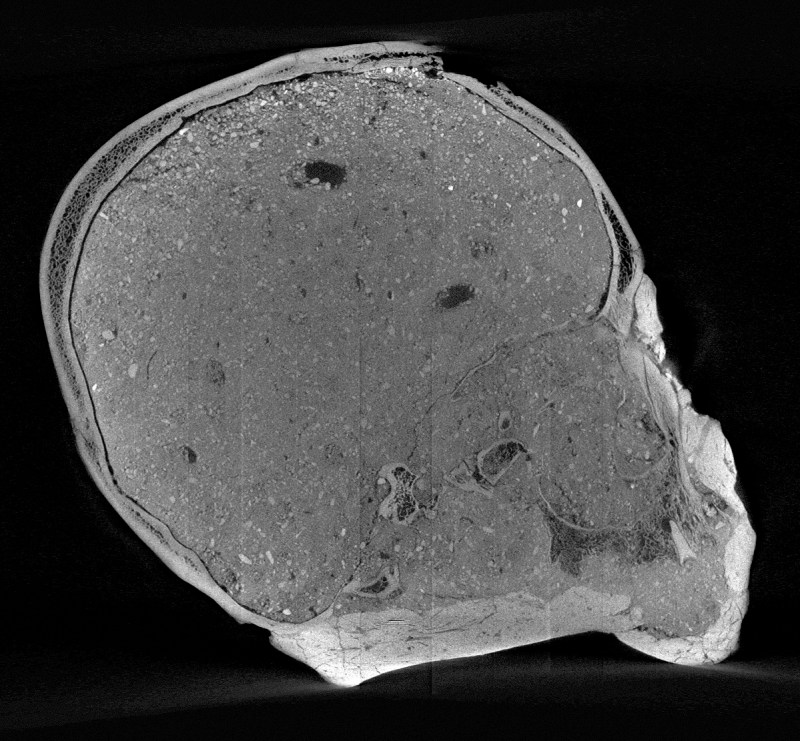

This reconstruction was handled by the Natural History Museum’s Imaging and Analysis Center, whose micro-CT scan of the skull laid the groundwork for a 3-D digital model of it that, for the first time, revealed the shapes of the skull’s palate, cheekbones, brow ridge, and eye sockets. From there, researchers were able to put together what they feel is an accurate representation of the man’s facial features.

In the case of the Jericho Skull, researchers found that he lacked a lower jaw (which may have been removed for the plastering process), as well as broken teeth and a healed broken nose. They also saw evidence of tight head binding, often applied to children for aesthetic purposes during that time.